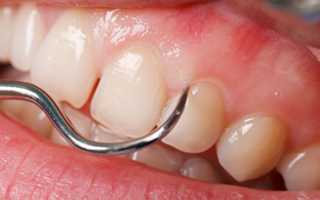

Фото 1. Стоматолог проверяет оголяются ли корни и шейка зубов у пациента, страдающего пародонтозом, при помощи зонда.